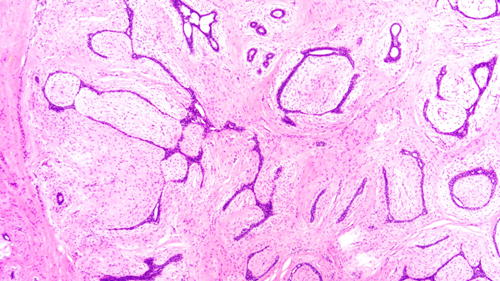

乳腺纤维腺瘤与周围正常腺体组织分界清楚,显微镜下可见其由良性的乳腺上皮和间质成分增生形成,细胞形态温和,无异型性。根据组织形态,可大致分为管内型和管周型,但分型对临床预后并无显著影响。该肿瘤经完整手术切除后,一般不会复发。

(图1:正常乳腺组织小叶)